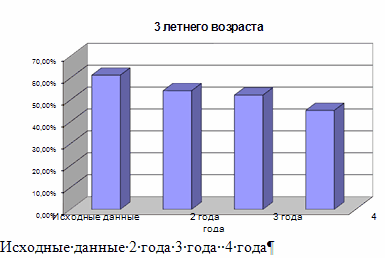

Чтобы профилактика давала наибольший эффект, необходимо одновременно воздействовать на все основные факторы риска в развитии зубов. Профилактика кариеса зубов препаратами фтора получила наибольшее распространение в мире, это - единственный метод, позволивший достичь реального снижения заболеваемости.

Но на территории Р.Ф. существуют и другие проекты, которые могут решить эту проблему. Например, в Воронежской началась программа создания фторосодерщащего молока. В результате которой стоматологические заболевания сократились